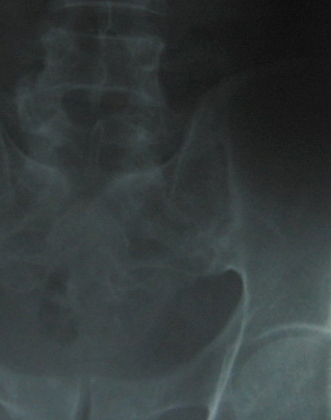

Fig.6 Left Sacro iliac joint A.P view -magnified